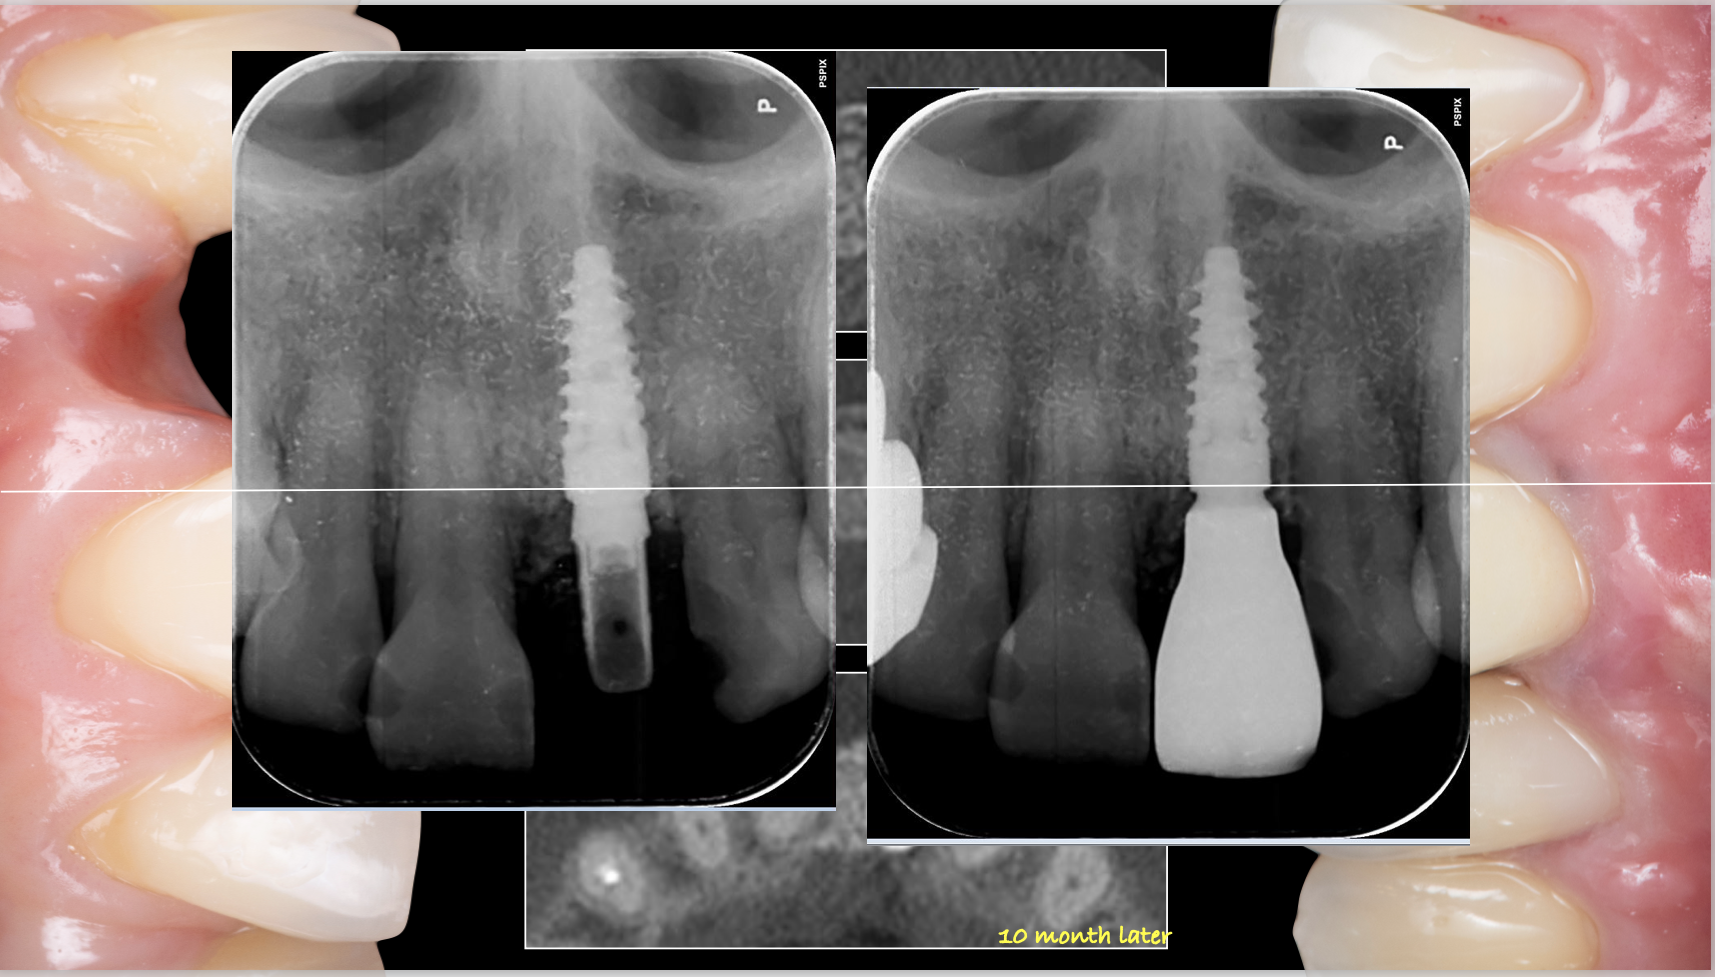

症例紹介29:インプラント治療/前歯_ソケットシール《50代女性》

治療内容:食事中に前歯が破折し、治療を希望し来院。

上顎:折れた歯を見ると、一部被せ物に歯が残っており保存不可能な状態。

上顎:歯には太い土台が入っており、折れて保存不可能な状態

リスク:残っている歯の一部を残してインプラントを入れることによって、歯茎が下がるのを抑えることができます。